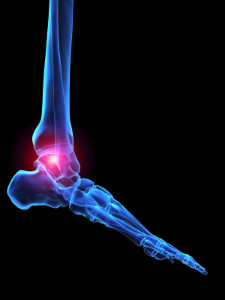

Ankle Osteoarthritis

Osteoarthritis (OA) is a condition that causes the cartilage that makes up your joints to deteriorate over time, making the bones rub against each other when you move. This causes pain, swelling, and a loss of function. Osteoarthritis often affects the ankle joints. There is no single known cause of osteoarthritis, but certain factors can increase your risk of developing the condition. Osteoarthritis is more common as we age, with older adults being at greater risk of developing OA. Being obese or overweight can put added strain on your ankle joints, and fat cells produce proteins that may make OA worse. Genetics can also play a role, as people with a family history of OA are more likely to have OA themselves. Injuries or repeated stress to the ankles, or having misaligned joints, can also raise your risk. If you are experiencing ankle pain and think that it may be OA, it is suggested that you seek the care of a podiatrist.

Arthritic Foot Care

Arthritis is a joint disorder that involves the inflammation of different joints in your body, such as those in your feet. Arthritis is often caused by a degenerative joint disease and causes mild to severe pain in all affected areas. In addition to this, swelling and stiffness in the affected joints can also be a common symptom of arthritis.